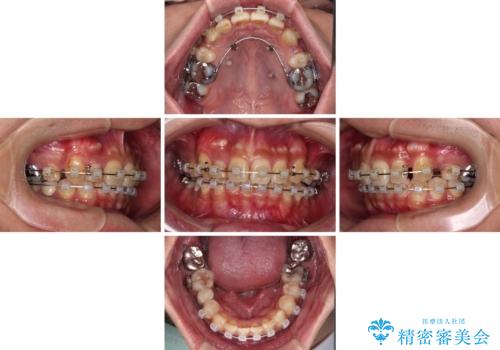

- クリアブラケット

- 2年8ヶ月

- 10-30回

補助装置を併用することで効率的に八重歯や正中位置の改善を達成することができました。